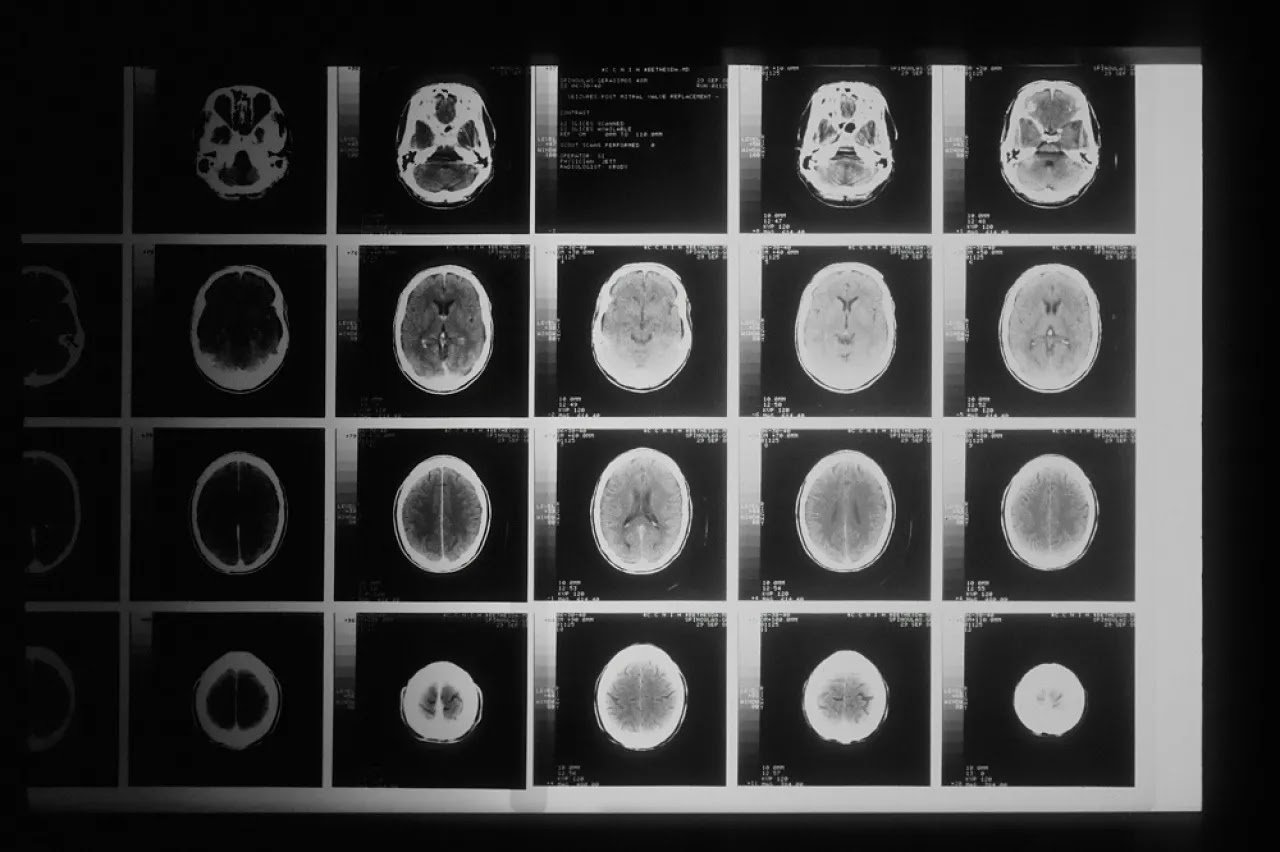

El glioblastoma es un agresivo tipo de cáncer cerebral que representa un desafío significativo para el tratamiento debido a su naturaleza agresiva y capacidad para crecer y diseminarse rápidamente.

Se trata del glioblastoma, un tipo de cáncer en el cerebro altamente agresivo cuyo pronóstico es generalmente desalentador.